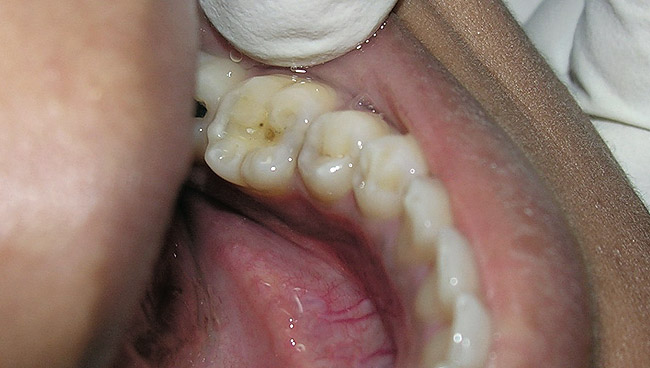

Figure 6  Clinical applications of RBCs for posterior restorations: occlusal caries restored with silorane-based RBC

Figure 6

The search for an ideal direct esthetic restorative material is still ongoing. Among the array of RBC materials, some are readily available in the market (flowable, packable, and fiber-reinforced), others have just recently been introduced (siloranes-based), and a few are still in development phase (fluoride-releasing). Individual properties of different RBC materials define their advantages, disadvantages, and clinical uses. Each type of RBC material has its own virtues in some clinical aspects and shortcomings in other aspects. Every material possesses either one or the other ideal properties of a restorative material, but not all of them. Therefore, it is important for a clinician to use every material judiciously and for a clinical application for which it is best suited (Figure 5, Figure 6, Figure 7, Figure 8, Figure 9 and Figure 10).